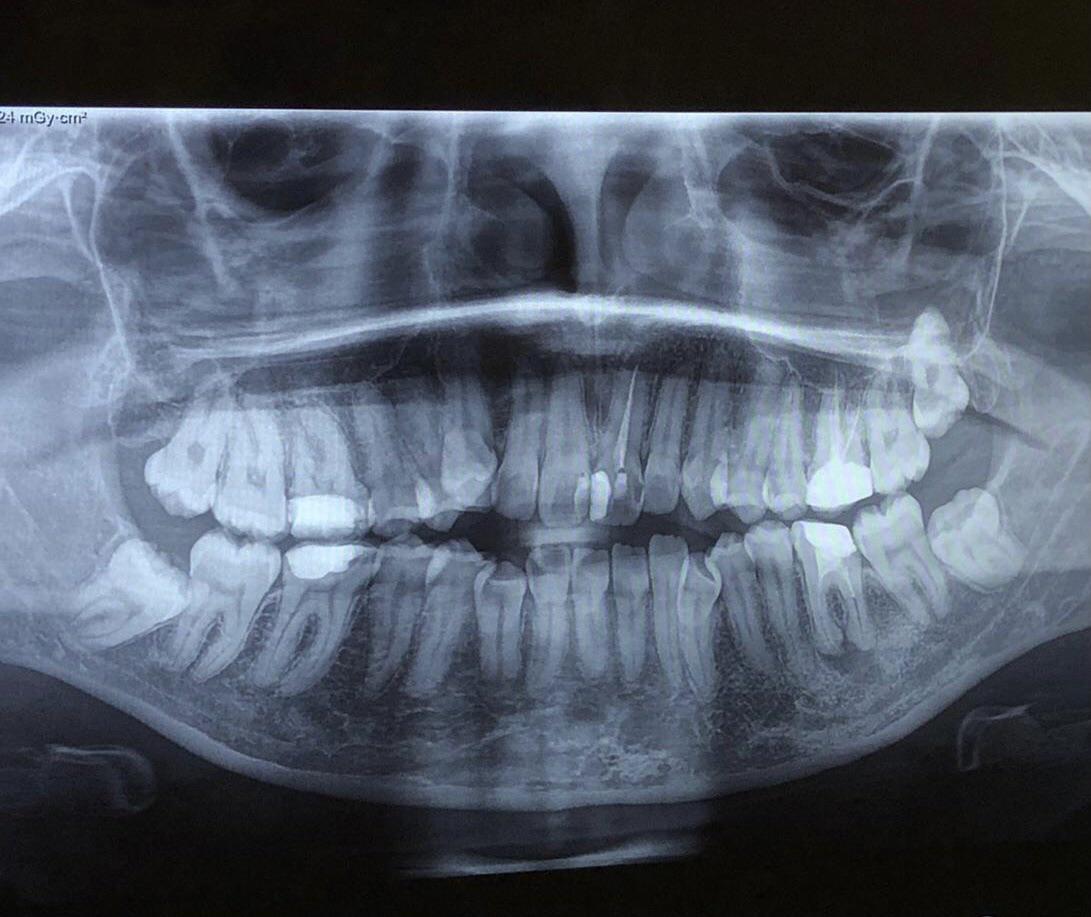

Can these wisdom teeth erupt after braces ? r/askdentists Can Braces Cause Wisdom Teeth To Erupt When wisdom teeth do erupt, you can expect at least some mild discomfort as the cusps cut through the sensitive gum tissue. While wisdom teeth can affect the alignment of your teeth after braces, there are several ways to mitigate these risks. Extracting wisdom teeth after braces are removed will not undo the. And within months we can lose all. Can Braces Cause Wisdom Teeth To Erupt.